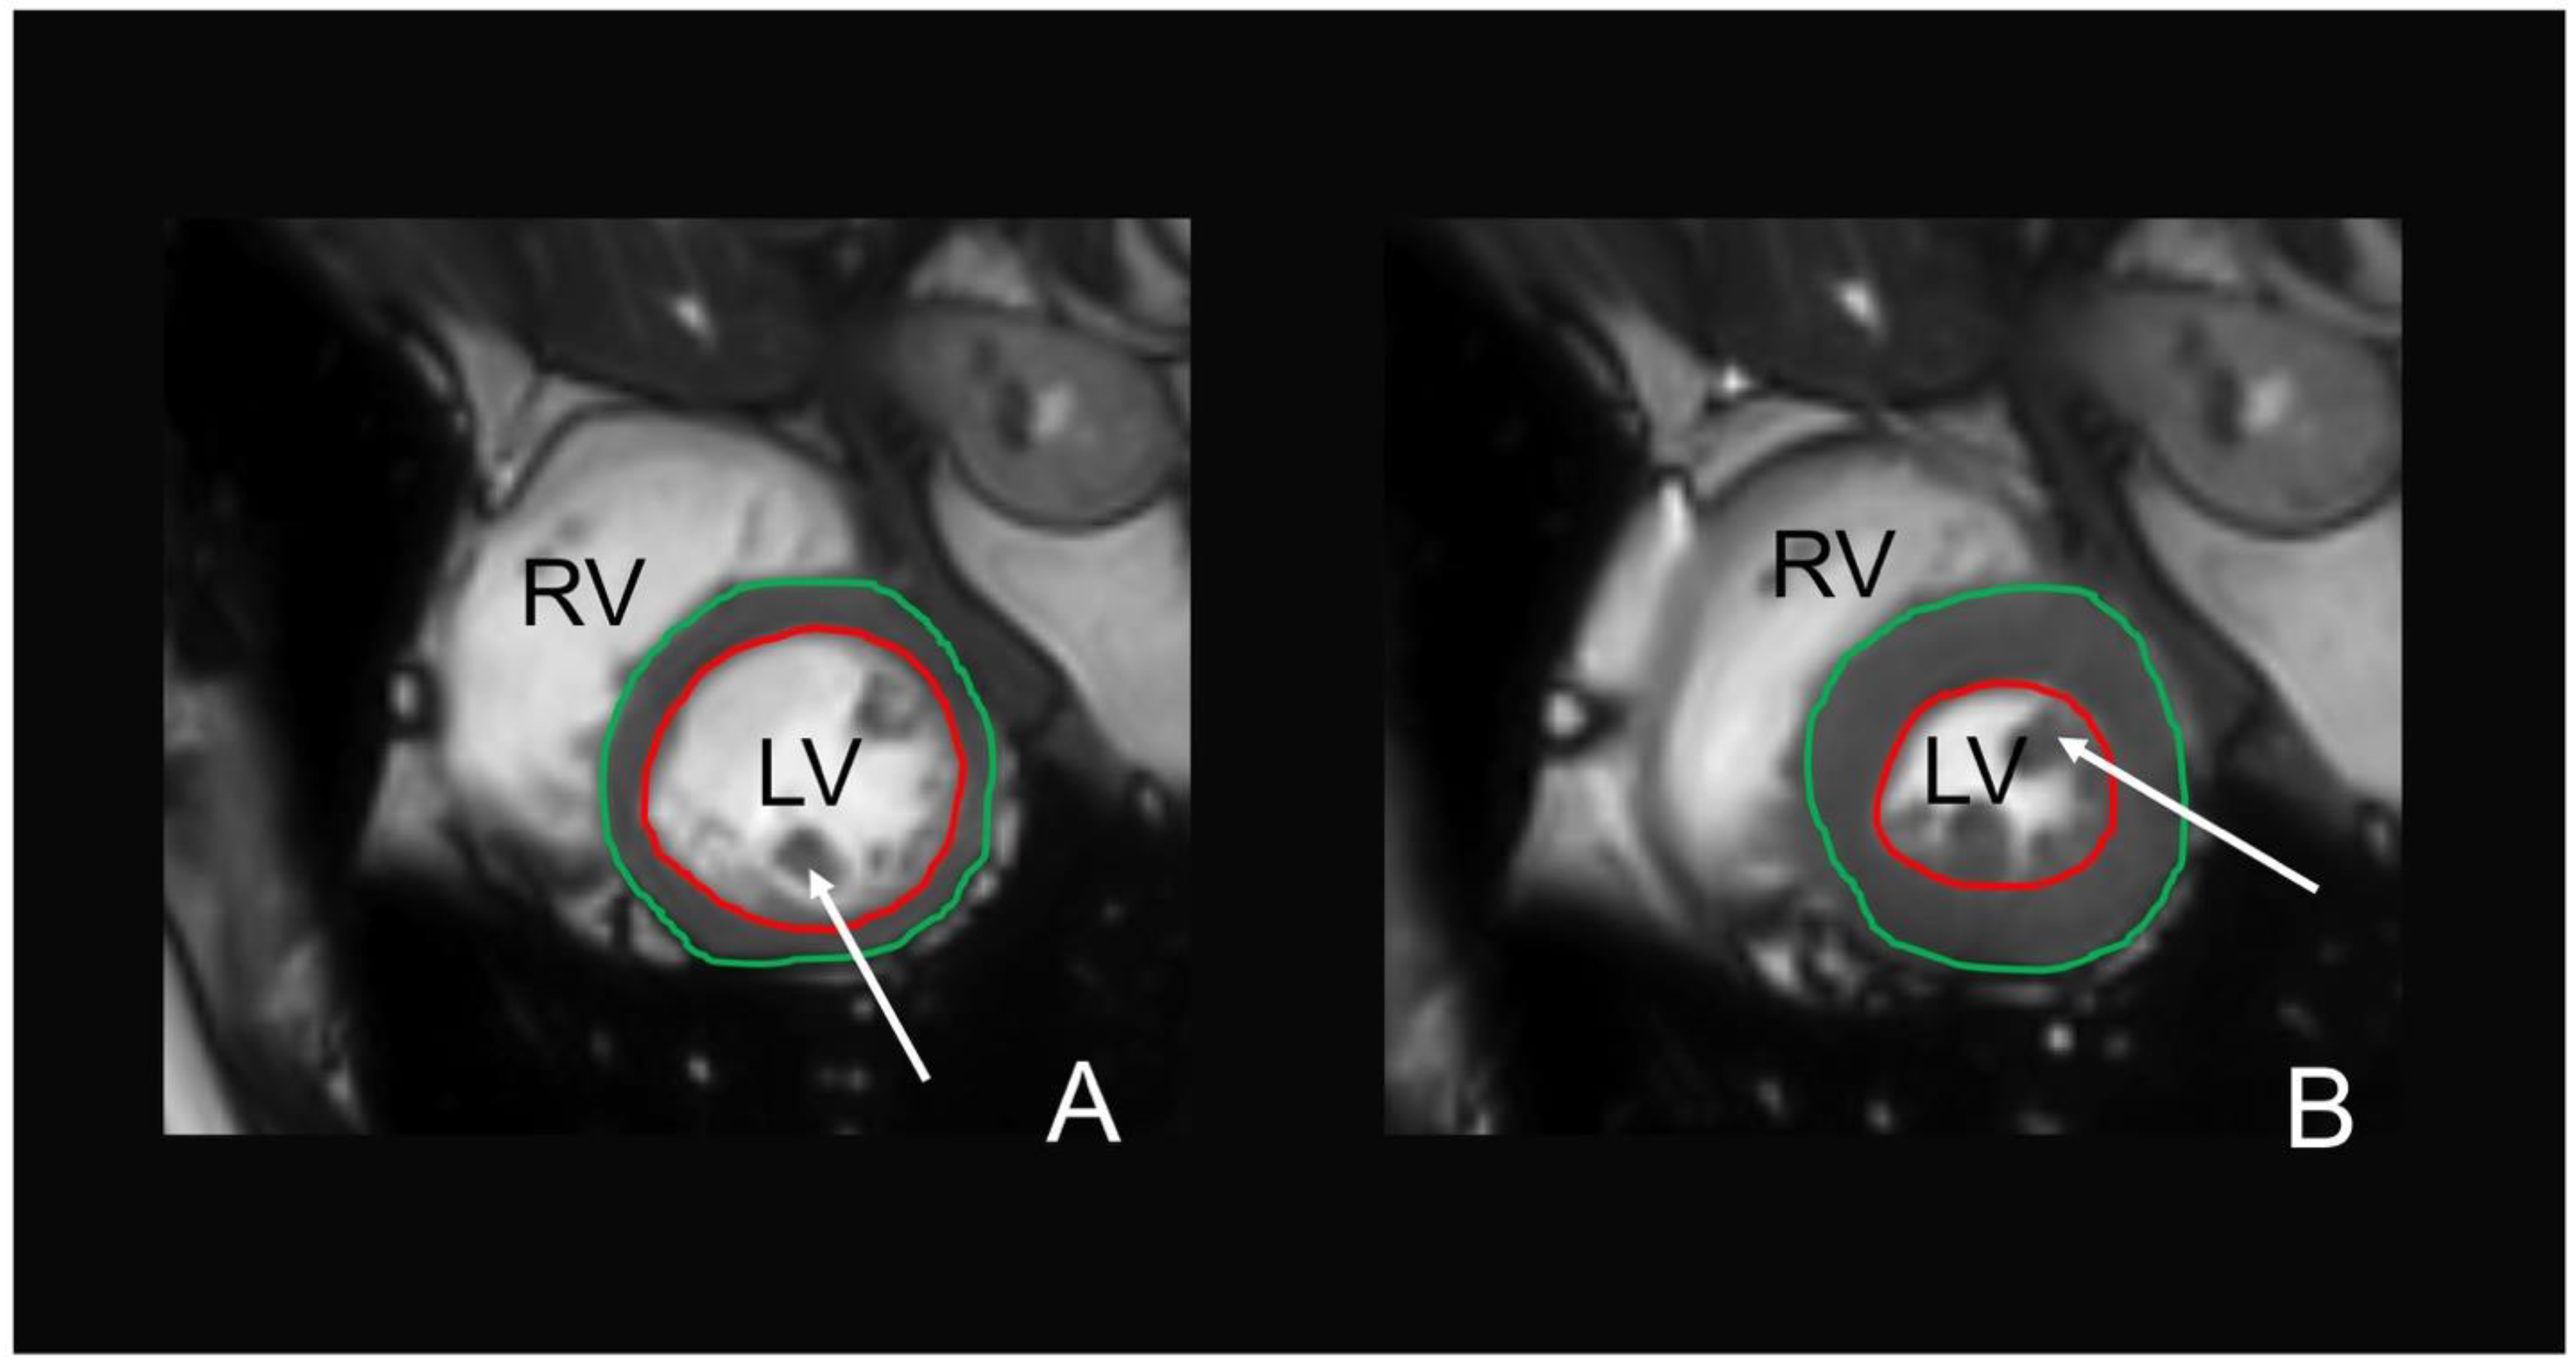

Evaluation of cine-SSFP sequences on cardiac MRI to obtain left ventricular (LV) function was performed semi-automatically using commercially available software (cvi42, Circle Cardiovascular Imaging, Calgary, Alberta, Canada) [27]. The reading was performed by two alternative readers, who were blinded to any information regarding the subjects’ characteristics and according to standardized postprocessing guidelines of the Society for Cardiovascular Magnetic Resonance [42]. Automatic contour detection was performed of the LV endocardial and epicardial border and corrected manually, if necessary. The papillary muscles were excluded from the myocardial mass and included in the ventricular volumes. The end-diastolic and end-systolic phases were identified automatically by the software. LV volumetric data included end-diastolic and end-systolic volumes with calculated stroke volume (end-diastolic volume minus end-systolic volume), ejection fraction ((stroke volume/end-diastolic volume)*100), and myocardial mass. A representative example of the LV contouring is given in Figure 2. Filling and ejection rates were quantified by using dedicated in-house software (pyHeart). This software displays the LV volume versus time curve along with its derivative and estimates peak gradients during early and late LV filling due to atrial contraction [43].

Figure 2.

MRI-based assessment of the left ventricular function on cine steady-state free precession (cine-SSFP) sequences in a 56-years-old female. The endocardial (red contour) and epicardial (green contour) border were detected automatically in end-diastole (A) and end-systole (B) and manually corrected, if necessary. The papillary muscles (white arrows) were included in the left ventricular lumen. LV = left ventricle, RV = right ventricle.